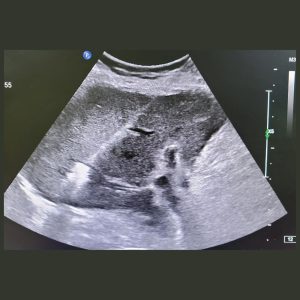

3. Tumor Ablation (Radiofrequency/Microwave)

The Problem: Small to medium-sized tumors in the liver, kidney, lung, or bone that need to be destroyed.

Our Solution: Under precise CT or Ultrasound guidance, a thin probe is inserted directly into the tumor. The tip then emits either radiofrequency (heat) or microwave energy, completely destroying the cancerous cells in a controlled zone.

Patient Benefit: A true scarless “surgery” that eradicates tumors without an incision. It preserves maximum healthy organ function and is often a curative option for early-stage cancers.